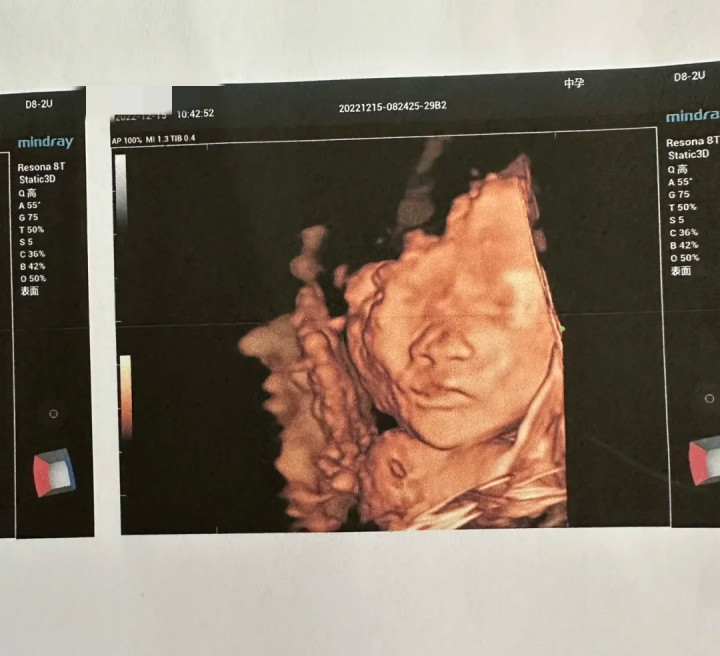

孕22周大排畸这天,他们特意选了一家允许爸爸进入B超室的医院。医生在慧慧肚子上涂上耦合剂,拿起探头滑动。宝宝很“配合”,先是小脚丫,再是小屁股、又看到孩子的整个背部,还看到孩子的后脑勺,最后面,孩子终于把脸露了出来。

而慧慧的老公看到孩子的脸也是非常的兴奋,开云官方体育app还跟慧慧说:唉呀,这个眼睛看起来就像我的,这鼻子有点像你的蛮高的,就在这时孩子突然咧着嘴笑了。

医生缓缓说道:“这孩子不一定能要。 B超显示宝宝是‘兔唇’,也就是唇腭裂,嘴上咧着并不是在笑,而是因为上唇是裂开的。”